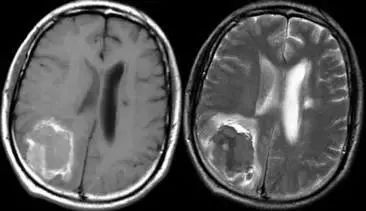

图片

脑出血亚急性早期

T1 低信号核,高信号环(左),T2 低信号(右)